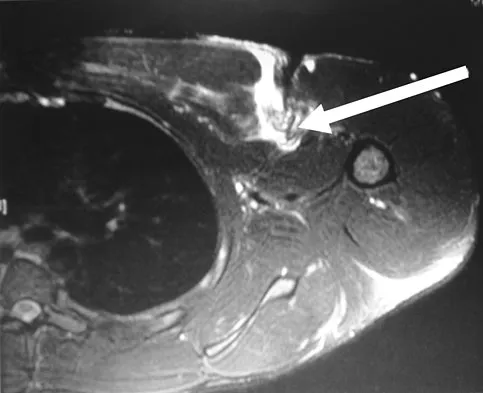

A 35-year-old woman who is a recreational runner reports posterior knee pain and tightness in the knee with flexion during running. She denies any history of trauma. Examination reveals normal patellar glide and tilt and no patellar apprehension. Range of motion is 5 degrees to 120 degrees, and quadriceps function and knee ligamentous examination are normal. Radiographs are normal. An MRI scan is shown in Figure 18. What is the most likely diagnosis?

Explanation